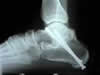

Forefoot and rearfoot surgery

Many foot problems do not respond to “conservative” management. Dr. Shingledecker can determine when surgical intervention may be helpful. Often when pain or deformity persists, surgery may be appropriate to alleviate discomfort or to restore the function of your foot.